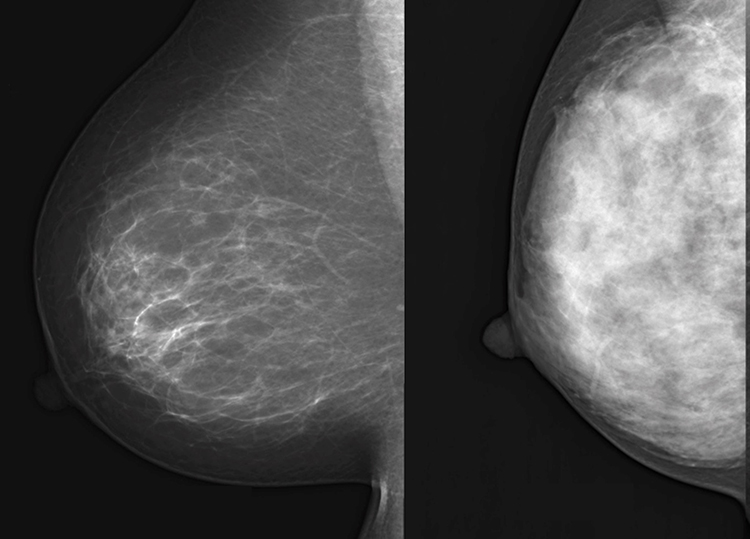

高濃度乳房(右)では、がん細胞が隠れて見えづらくなりやすい